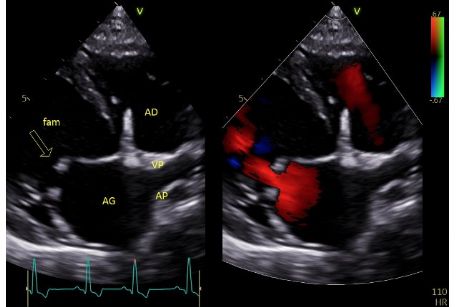

La dysplasie mitrale sténosante, présente les 4 principales caractéristiques échocardiographiques suivantes :

1. Des feuillets mitraux hyperéchogènes et épaissis de mobilité réduite (Figure 9) ayant pour conséquences l'association d'une insuffisance mitrale et d'une sténose mitrale modérée, cette dernière expliquant la composante diastolique du souffle à l'auscultation cardiaque (Figures 8A et 8B, Vidéo 5).